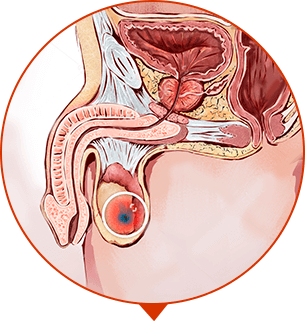

Revolution in der Behandlung der chronischen Prostatitis

20 Tausende Männer in Europa haben schon über den Schmerz und die Probleme der Harnentleerung vergessen

SCHRITT 2

Harnentleerung wird stabil, nicht häufig, entfernt die Entzündung

-

SCHRITT 3

regeneriert sich die Erektion, der Körper befestigt sich, Prostatitis kehrt nicht zurück

Der Schmerz quält Sie. Prostatitis stört Sie. Es kann Ihnen noch schlechter in den nächsten 1 - 2 Jahre werden. Infertilität. Blut bei der Ejakulation und Harnentleerung. Urinstau in der Blase (bis 500 ml). Vesikulitis.

IMPOTENZ

Unheilbare Mannesschwäche

ADENOM DER PROSTATA

Gewebsvermehrung der Prostata, Bildung des Tumors und “der Knoten”

ONKOLOGIE

Bösartiger Tumor, die häufigste Ursache des Todes der Männer